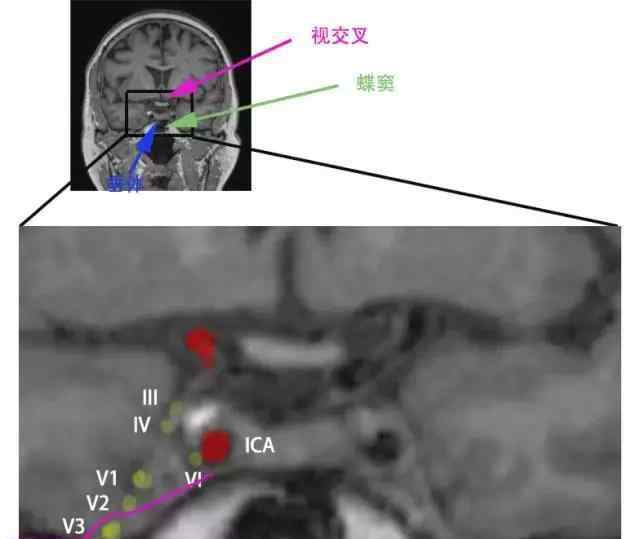

海绵窦这一构造内部构造多,但算不上太繁杂。在冠状位上看,海绵窦便是一所小屋子,来来去去许多 群体,有颈内动脉、颈内动脉周边交感丛和第III、IV、V、IV对中枢神经。

在冠状位上看海绵窦如同一所小屋子(图1):一屋分两截,脑垂体当吊顶灯,神经系统毛细血管屋子里坐,蝶窦超级变身大红门,颈内动脉房外还作烟筒。在其中,绝大多数神经系统靠两侧坐,从上向下分别是眼动、滑轮和三叉神经V1、V2支,外展神经则与颈内动脉牢牢地偎依。这一房屋水准5~7mm,垂直5~8毫米,前后左右10~15mm,确实不大,大家医院门诊基本的MRI扫描仪T1相间距5毫米,类似也就能见到一个方面。

依据海绵窦的好多个隔壁邻居,例如脑垂体、蝶窦、视交叉,在冠状位大部分就能寻找海绵窦这一小屋子了(图2)。尽管三叉神经下颚支(V3)也可以见到,可是V3不历经海绵窦内,只是在进海绵窦以前的Meckel’s Space里就分出来;因而,好运气的情况下在海绵窦冠状位还能够见到V3向外正下方的神经系统进到颞肌,如同图2。Meckel’s Space详细信息能看《三叉神经解剖——被四大核团掌控的一双胖子手》。

记忆力这好多个神经系统在海绵窦内的部位也不会太难,大伙儿能够看见图1或是图2,依据这好多个颅神经的序号(3眼动、4滑轮、5三叉、6外旋),从小到大,左边依照反方向排序,而右边就按顺时针排序,便是这好多个颅神经在海绵窦内的部位。